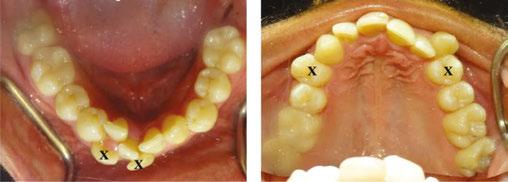

The intraoral examination revealed moderate maxillary crowding and severe mandibular anterior crowding, Class I molar relationship, occlusal cant (Figure 2D), and an ectopic upper left canine (Figure 2E). Both arches displayed discrepancies in arch length, particularly the mandibular arch, and each showed tapered arch forms (Figures 2A and 2B). A Bolton discrepancy was also noted. A Class IV composite restoration was also present on tooth No. 8.

It was clear that extractions were going to be necessary to relieve crowding for this patient. It was unclear which mandibular teeth would be best suited for extraction, considering that tooth Nos. 24, 26, and 27 were ectopic and considerably displaced out from the center of the alveolar housing or trough (Figure 2B). Additionally, tooth No. 24 was already showing signs of gingival recession (Figure 2D), further suggesting its position within the alveolar housing was compromised.

The CBCT image revealed several findings. First, it was apparent that a periapical radiolucency (PARL) existed in association with the overlapping mandibular incisors (Figures 4A – 4C). Figure 4A shows tooth No. 24 with compromised facial alveolar support, while figure 4C shows tooth No. 25 with a greater amount of visible facial bone. In figure 4E, tooth No. 27 is proclined and has compromised facial alveolar support. Lastly, a second PARL was noted surrounding tooth No. 8 (Figure 5).

The established treatment plan and extraction recommendation for this patient was primarily based on the CBCT image findings with regards to alveolar support and space analysis. It was clear that tooth No. 24 had the least alveolar support and was already experiencing gingival stripping. However, extraction of this tooth alone would not provide enough space to relieve the crowding, as it is already entirely blocked out of the arch. If one were to extract tooth No. 28 also, tooth No. 27 would need to be distalized and retracted into the arch to allow room for the alignment of the remaining incisors. A potentially more efficient plan would be to extract the periodontally compromised tooth No. 27, as its root is already significantly dehisced thru the facial cortical plate making room for proper alignment of tooth No. 26. Therefore, the final treatment plan for this patient is as follows: refer to general dentist or endodontist for evaluation of PARLs on tooth No. 8 and No. 25 (Figures 4A, 5A, and 5B) and extraction of Tooth Nos. 5, 12, 24, and 27 (Figures 6A and 6B).